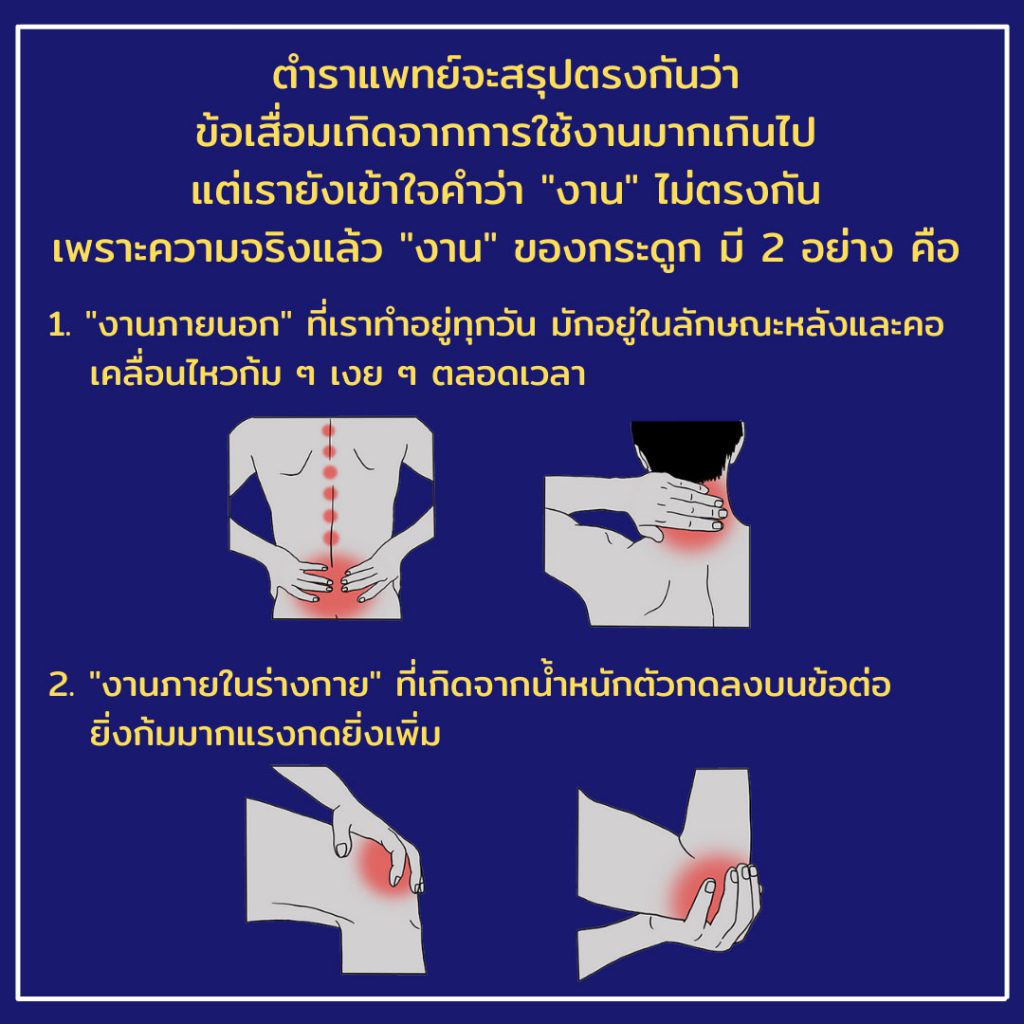

ความน่ากลัวของโรคกระดูกพรุนและอาการขาดแคลเซียม คืออันตรายที่เป็นภัยเงียบอย่างแท้จริง เพราะปกติแล้วในช่วงอายุระหว่าง 30-35 ปี ร่างกายจะมีทั้งขั้นตอนของการ “สร้างและสลายกระดูก” ที่สมดุลกัน แต่เมื่อวันเวลาล่วงเลยจนเข้าสู่ช่วงอายุ 40 ปี ขั้นตอนการสลายกระดูกจะเริ่มมีมากกว่าการสร้างอย่างชัดเจน หรือพูดได้ว่า “ครึ่งชีวิตของเรา ล้วนอยู่กับขั้นตอนการสลายกระดูกตลอดเวลา”

ขั้นตอนต่อมาเมื่อกระดูกสลายไปเรื่อยๆ เราจะเริ่มรับรู้ถึงสภาพโครงสร้างแสนจะเปราะบางในตัว เพียงการกระแทกเบาๆ หรือการไอ-จาม จนเกิดบิดเอี้ยวตัวกะทันหัน ก็มากพอที่จะทำให้กระดูกแตกหักได้แล้ว และยังมีโอกาสสูงมากที่จะเกิดการแตกหักครั้งที่ 2 หรือ 3 ตามมา สิ่งเดียวที่มนุษย์สามารถชะลออาการธรรมชาตินี้ได้ จึงมีเพียงการเสริมแคลเซียมให้กระดูกเท่านั้น